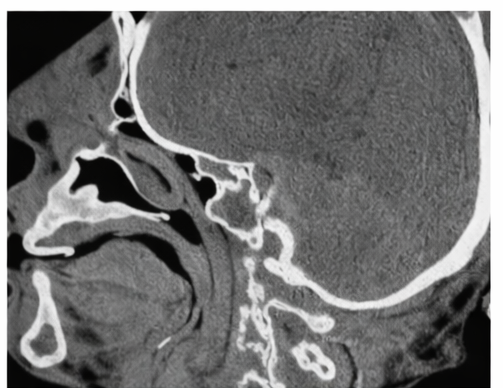

Contrast-enhanced computed tomography of the neck demonstrated diffuse inflammatory involvement of the submandibular and sublingual spaces, characterized by soft tissue edema and prominent fat stranding, without evidence of a well-defined or drainable abscess collection. Imaging also showed elevation and posterior displacement of the tongue with resultant narrowing of the upper airway due to surrounding soft tissue swelling. These radiological findings, in conjunction with the clinical presentation, were consistent with the diagnosis of Ludwig’s angina and highlighted the significant risk of airway compromise, underscoring the need for urgent and aggressive management.

The hallmark clinical features include painful submandibular swelling, induration of the floor of the mouth, tongue elevation, dysphagia, drooling, and respiratory distress. Imaging, particularly contrast-enhanced CT, is useful in assessing disease extent and identifying abscess formation, although treatment should not be delayed in unstable patients [4,5].